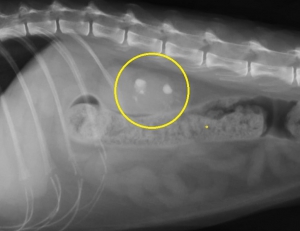

下のレントゲン像の黄色の縁で囲んだ目立たない結石は画像でこそ目立ちませんが、急性の尿管閉塞を生じている尿管結石です。尿管閉塞というのはお腹の中で腎臓から膀胱をつなぐ細い尿管で生じます。尿路閉塞として一般的な膀胱結石による尿道閉塞とその仕組みは同じです。